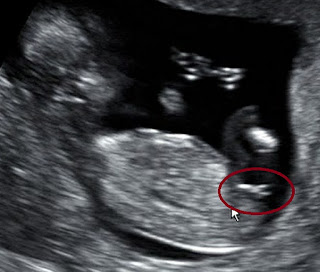

Ao rever a eco pela enésima vez (tenho saudadinhas de ver o meu bebé...), reparei noutra imagem em que é possível ver o sexo. O médico tinha dito que tinha visto numa outra imagem, mas eu não percebi qual na altura. Logo quando vi pensei que se tratasse de uma piloca, mas, com uma pequena pesquisa na internet e nos livros, percebi que é mesmo menina.

Ora, dizem os entendidos que o tubérculo genital é muito semelhante em ambos os sexos nesta fase, com a diferença na posição. O tubérculo masculino faz um ângulo de, pelo menos, 30º com a coluna, enquanto que o feminino fica paralelo à mesma.

Mais paralelo impossível, certo? Por isso é que nos meninos se consegue ver de frente e nas meninas não.